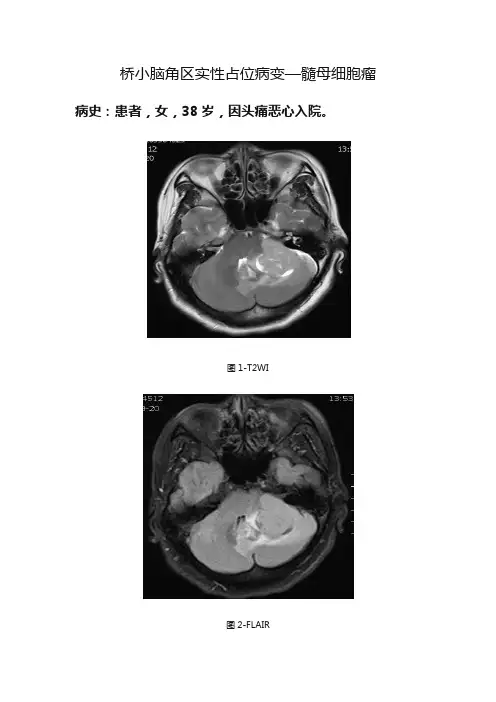

桥小脑角区实性占位病变—髓母细胞瘤病史:患者,女,38岁,因头痛恶心入院。

图1-T2WI图2-FLAIR图3-T1WI轴位图4-T1WI轴位增强图5-T1WI冠状位增强图6-T1WI矢状位增强图7-T2WI矢状位图8-DWI图9-ADC 基本解剖影像:图10-normal图10为所示病例同层面轴位正常T2WI图片,黄色箭头所示为正常耳蜗长T2信号,棕色箭头所示为正常听神经稍长T2信号,MRI图像中骨质因不含自由水呈低信号,无法显示内听道骨质结构,蓝色箭头所示为桥小脑角池长T2信号,其内无异常信号影,其内线形低信号为听神经及小血管流空信号影。

图1-T2WI图2-FLAIR图4-T1WI轴位增强T2WI、FLAIR、T1WI增强:蓝色箭头所示左侧内听道未见增宽,左侧听神经走行、形态正常。

白色箭头所示病灶形态不规则,似呈宽基底,与小脑半球及桥小脑角区之间见脑脊液信号,桥脑左侧、第四脑室、左侧小脑半球组织受压推移,边缘可见水肿信号;病灶增强中等强化,其内信号不均匀,可见小片状低强化。

黄色箭头可见与病灶强化相同条形异常信号与小脑蚓部关系密切。

影像描述:双侧内听道未见增宽,双侧听神经走行、形态正常。

左侧桥小脑角区见不规则形实性占位,边界清晰,呈稍长T1信号稍长T2信号,FLAIR未见信号减低。

增强中等强化,其内见小片状低强化影。

DWI呈稍高信号,ADC稍低信号。

临近左侧小脑半球、第四脑室受压变形。

周围见片状水肿信号。

影像诊断:左侧桥小脑角区实性占位病变,考虑脑膜瘤。

分析思路:本例为误诊病例,重点探讨面对典型病例不典型部位的诊断方法。

临床中经常看到典型病例不典型表现及不典型部位,那么面对此类病例,如何拓展思维提高诊断正确率是需要思考的问题。

本例分析思路如下:1.临床病史,未提示左耳听力改变,听神经瘤概率减低。

2.年龄:本例为青年女性,髓母细胞瘤概率减低,脑膜瘤、听神经瘤、室管膜瘤可能。

3.部位:病灶位于桥小脑角区,内听道未见增宽,听神经走行、形态未见异常,可以除外听神经瘤。